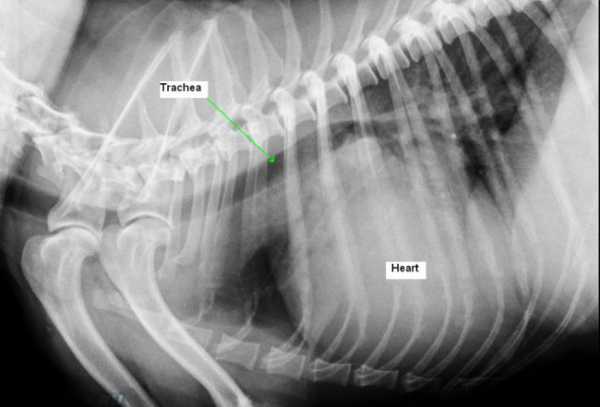

- Рентгенограмму. При ее выполнении обращают внимание на изменение размера органа и наличие застойных явлений в легких.

● Рентгеноскопия для определения размеров как самого сердца, так и основных кровеносных сосудов, а также изменений в легких и в дыхательных путях

- Рентгенологическое исследование – надежный проверенный способ оценить размеры сердца и состояние легких. На рентгеновском снимке мы так же сможем увидеть признаки скопления жидкости в грудной или брюшной полостях, что, несомненно, поможет врачу в постановке правильного диагноза.